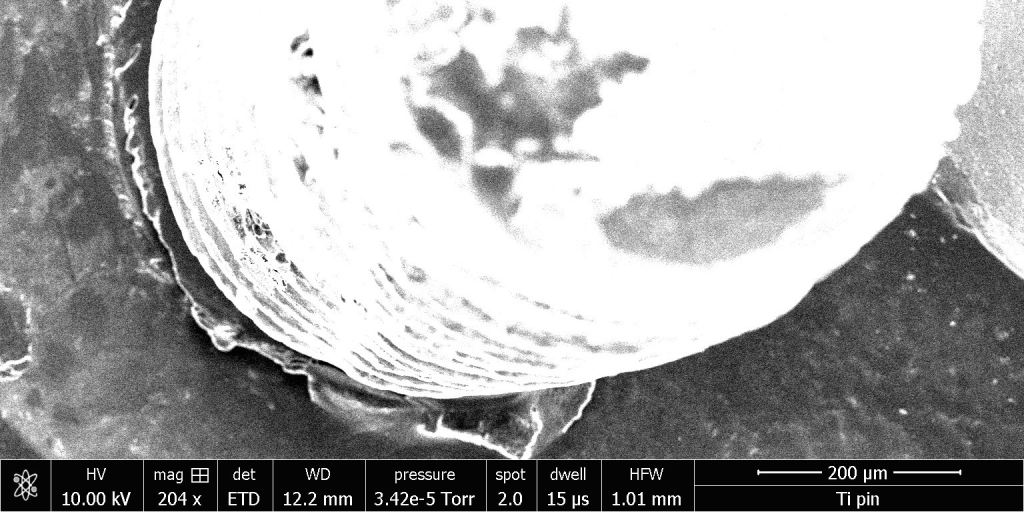

Electron Microscope Photos

Comparing Titanium Pin to Fiber Optic Pin